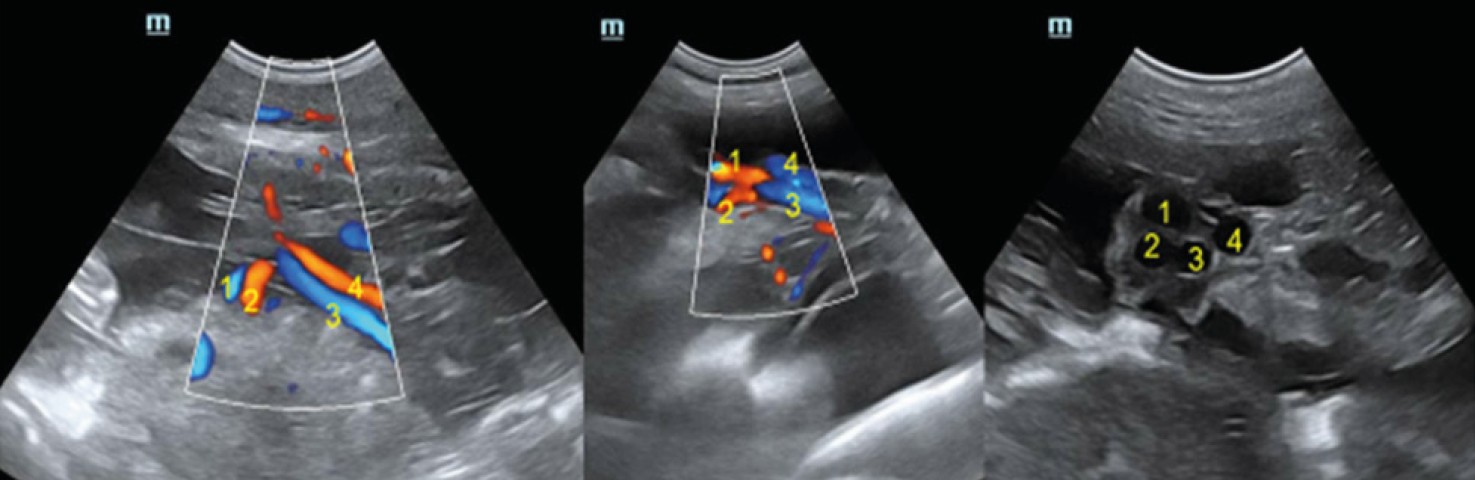

Fig. 5. Scanning of umbilical cord vessels in a dog fetus in color Doppler and B-mode. The numbers indicate the vessels of the arterial (2, 4) and venous (1, 3) beds

Source: compiled by N.I. Kolyadina, A.V. Shumeyko on the Mindray Vetus 8 Ultrasound Machine.